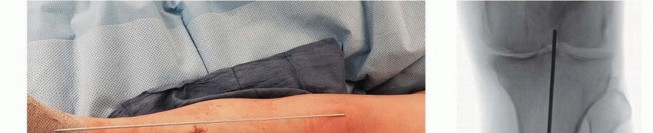

--- - TECH FIG 3 • A partial medial parapatellar arthrotomy that is carried into the intermedius allows enough subluxation of the patella to perform semiextended nailing. (Courtesy of Paul Tornetta III, MD.) Dissect synovium from retinaculum; divide retinaculum sharply. ### Standard Intramedullary Nailing Initial Guidewire Placement Drape the leg free, including the proximal thigh. Draping the leg more distally can limit knee flexion due to bunching of the drapes. Flex the knee over a bolster or radiolucent triangle. A padded thigh tourniquet can be applied and inflated during the surgical approach, but it must not be inflated during reaming because of the risk of thermal injury to the intramedullary canal. For this reason, a thigh tourniquet is usually omitted.